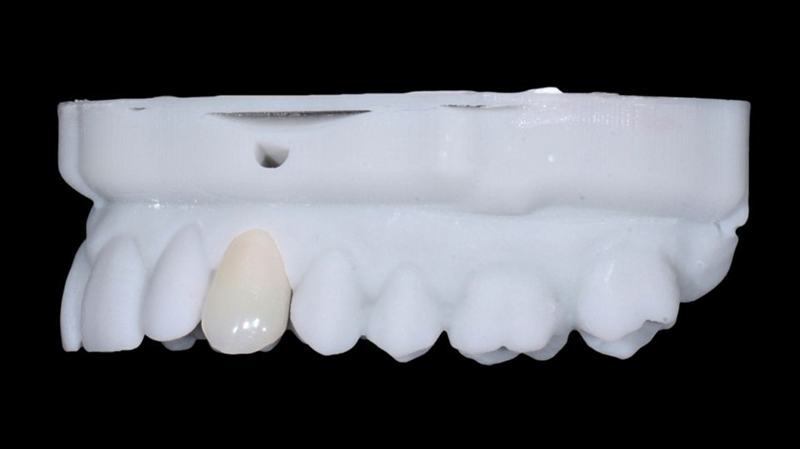

与此同时,12号牙齿的陶瓷贴面也已准备好并准备进行粘接。两种最终修复体均采用打印树脂模型接收,这使我们能够直观地看到最终结果(图 55-56)。

Fig. 55: Printed resin model with ceramic veneer and crown in position.

Fig. 56: Occlusal view of the crown on the model: note the exact positioning of the screw hole due to the precise implant placement with...